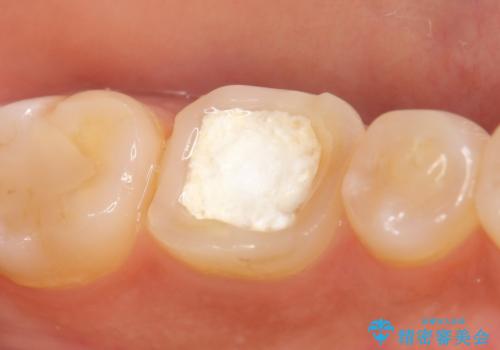

検査の結果左下6は神経が死んでいたため、根管治療を行いました。

その後症状の緩解を確認後、オールセラミッククラウンによる補綴を行いました。